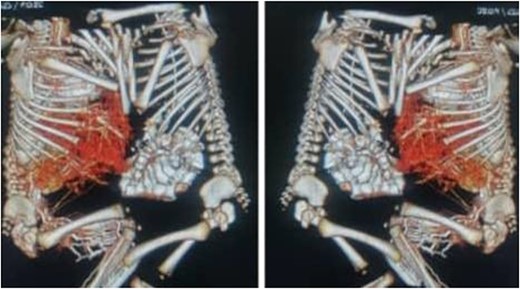

A computed tomography scan revealed ventral omphalopagus-xiphoid union of conjoined twins with separate vital organs and signs of fusion of the anterior aspect of the livers (adhesion), as well as one lower limb arteriovenous malformation (AVM) (AV fistula) seen extending from external iliac major vessels in both with difference in affected side (Fig. 3). Both twins’ echocardiography scans were completely normal. Both the complete blood count and the liver function test were normal.

CT scan with contrast of case 2 showed omphalopagus type of conjoined twins with fusion of anterior aspect of the livers and separate other vital organs.